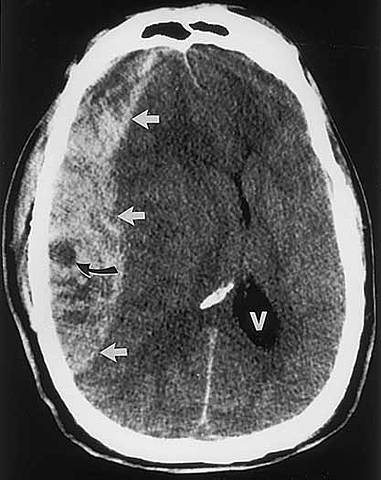

Logros alcanzados gracias a la inclusión de avances tecnológicos y de telemedicina o TAC (Tomografía axial).

Diferenciando y clasificando patologías ya conocidas.

Dichos avances contribuyeron a diagnósticos como (PET) y a la resonancia magnética (FMRI).